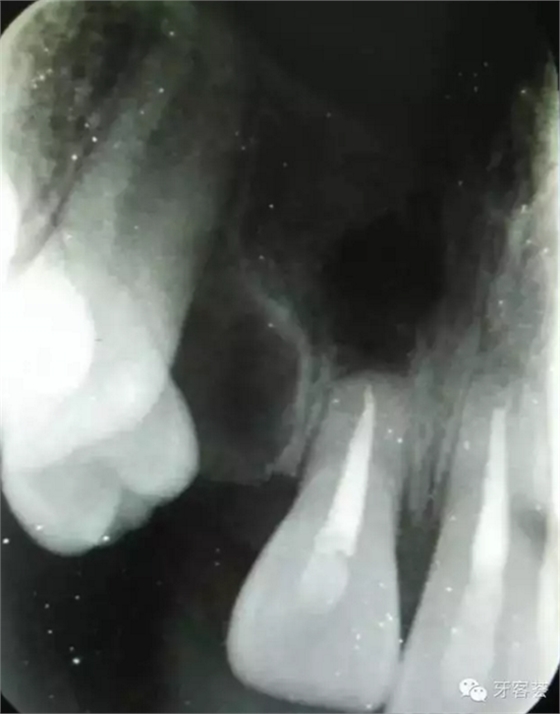

圖3:根尖片可以清晰看到11、21根尖橫折,這是根管治療過程中的試尖。